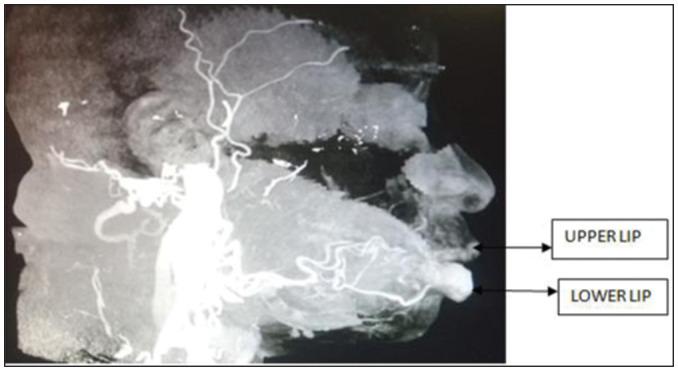

Calibre persistent artery of the lower lip is a vascular anomaly where the branches of the inferior labial artery maintain their size up to the submucosa of the lip. There is persistent pulsatile feeling, occasional ulceration, and recurrent bleeding. Doppler ultrasound and angiogram are used to confirm diagnosis. Before this case report, treatment of this condition has been surgical excision. We document the successful treatment with oral propranolol.

下唇口径恒定动脉是一种血管异常,下唇动脉分支直至唇部黏膜下层仍保持其大小。有持续的搏动感觉、偶尔的溃疡和反复出血。使用多普勒超声和血管造影来确诊。在本病例报告之前,这种情况的治疗方法是手术切除。我们记录了口服普萘洛尔成功治疗的病例。